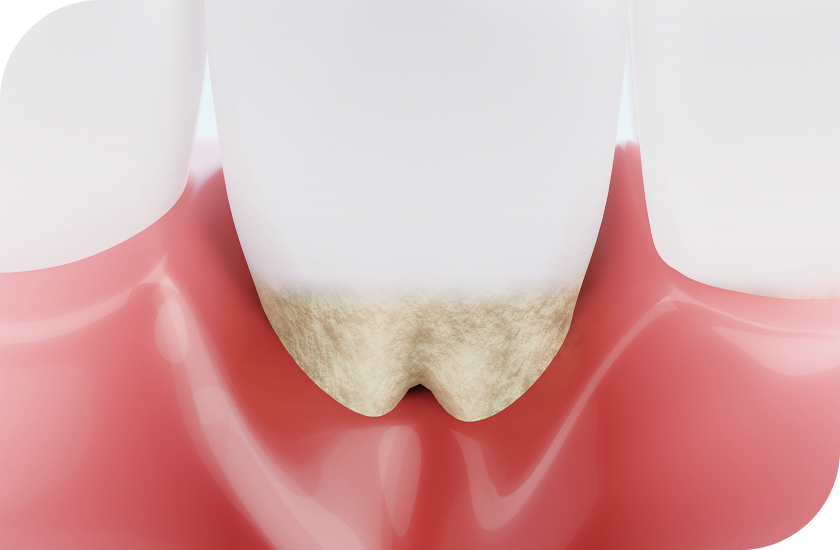

치아와 잇몸 경계 부위를 다듬어 이상적인 잇몸 라인으로

개선해주는 시술로 얼굴형, 치아의 크기, 입술 라인 등을 종합적으로 진단해

잇몸의 과도한 노출, 치아를 덮는 잇몸 조직, 잇몸 비대칭으로 인해

심미적 불만을 느끼는 경우

잇몸성형이 효과적인 해결책이 될 수 있습니다.